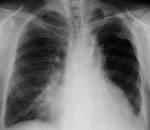

2. Второй подъем темп.до 39,9 от 08.02.2016. Госпитализ.в инфекционное отделение с DS:ОРВИ, Грипп, прикорневая пневмония КТтомограммой не подтвердилась. Назначены: Реленза, цефтриаксон, левомак, азитромицин, реосорбилакт и препараты, снижающие темп. Органы брюшной полости и почек - без структурных изменений.Выписан 19.02.2016 с нормальной темеп.